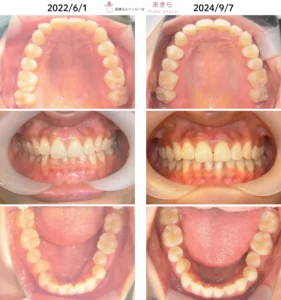

過蓋咬合 症例 嚙み合わせが深く前歯が見えないケース

症例写真

2022年4月28日⇒2024年10月7日(2022年5月プレオルソスタート)

2022年4月28日⇒2024年10月7日

- 2022年5月より「プレオルソソフト」タイプスタート

- 2023年4月に「プレオルソハード」タイプ変更

- 回数22回

- 日中1~2時間使用と就寝時の使用を厳守していただきました。

- プレオルソ拡大を随時行っております。

- 経過資料採得をして『SH療法』移行検討